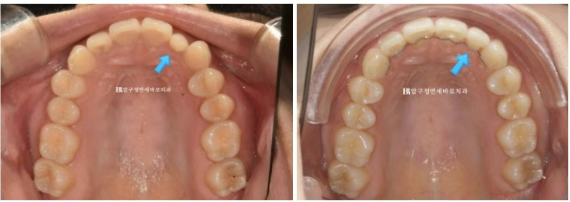

23.10

파란 화살표는 왜소치이고 앞니를 제외한 뒤쪽 어금니 배열은 양호합니다.

파란 화살표는 왜소치입니다.

덧니나 왜소치가 있는 경우라면 앞니 중심선이 그쪽으로 쏠려있는 경우가 많습니다.

앞니 부분교정에서는 중심선을 포기하는 경우가 많지만 이 왜소치를 정상 사이즈로 회복하는 라미네이트 치료를 하게 되면

중심선까지 맞춰서 마무리가 가능합니다.

따라서 앞니 부분교정 후에 왜소치 무삭제 라미네이트 치료도 추천드렸습니다.

23.10~24.05

파란 화살표 왜소치는 정상크기로 치료가 되었습니다.